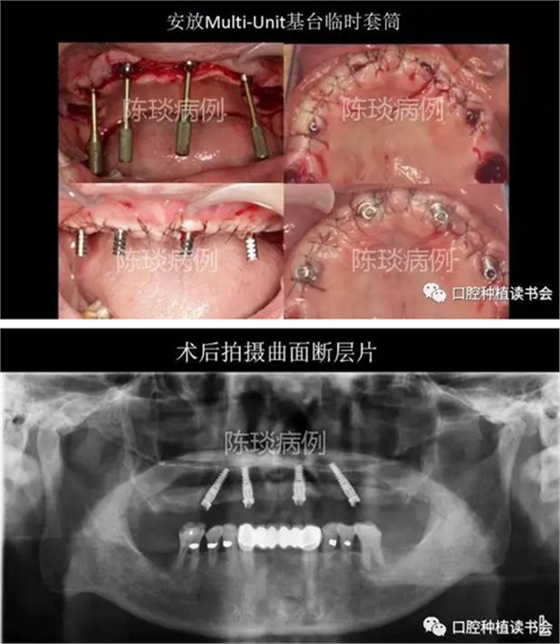

(1)數(shù)字化導(dǎo)板引導(dǎo)下完成種植體植入。

(2) 種植體植入術(shù)后制作臨時修復(fù)體即刻修復(fù)。